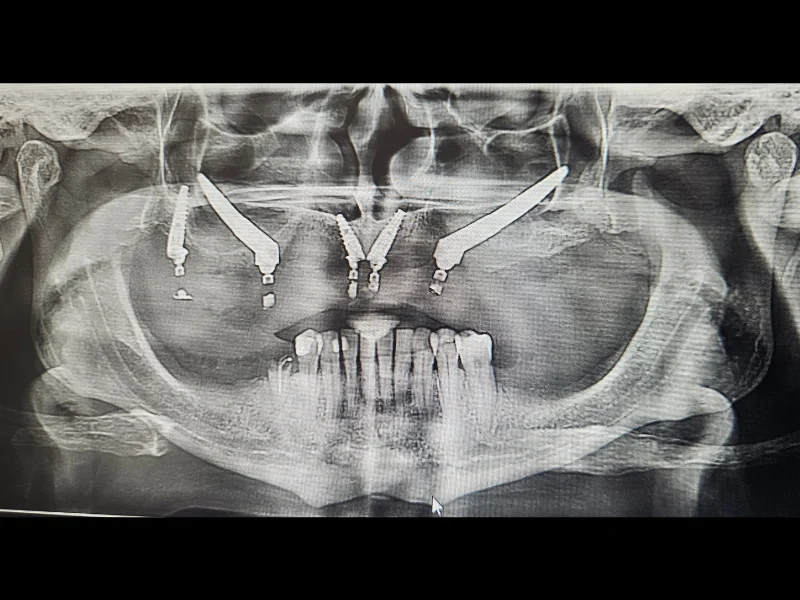

Za razliku od konvencionalnih implantata koji se ugrađuju u viličnu kost, zigomatični implanti se postavljaju u jagodičnu kost, koja je znatno čvršća i stabilnija. Na taj način omogućavamo fiksne zube i u slučajevima gdje druge metode nisu moguće, bez potrebe za složenim i dugotrajnim procedurama nadoknade kosti.

U zavisnosti od individualne anatomije i kliničke situacije, mogu se primijeniti i dodatne napredne tehnike poput transnazalnih, transsinusnih ili pterigoidnih implantata, čime se omogućava individualan i precizan pristup svakom pacijentu.

Prije zahvata se radi CBCT snimak, koji omogućava detaljnu analizu koštanih struktura i precizno planiranje položaja implantata. Nakon toga slijedi pregled kod oralnog hirurga i konsultacija sa anesteziologom, kako bi se obezbijedila potpuna sigurnost i kontrola tokom procedure.

Zigomatični implanti su posebna vrsta dentalnih implantata koji se ugrađuju u jagodičnu kost (zigomatičnu kost), umjesto u vilicu. Koriste se kod pacijenata koji nemaju dovoljno kosti za klasične implantate.